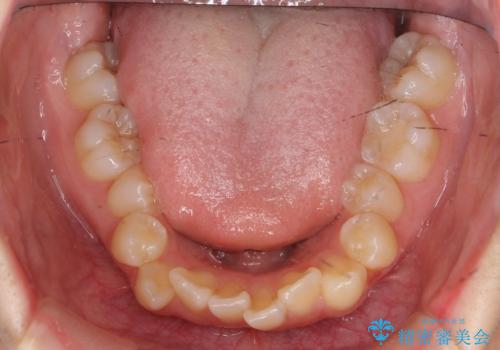

下の八重歯 歯を抜かずに インビザライン治療

- 歯並びのがたつきを主訴に来院。

抜歯してワイヤー矯正という選択肢も提案しましたが、マウスピース矯正で、歯を抜かずに並べてほしいとのことでした。

スペースを確保するために、歯をわずかに削る処置、奥歯を後ろに下げる処置(インプラント矯正)を行っています。

途中患者様のご都合で治療を中断していたため、長くかかっていますが、実質2年程度で終わる内容でした。